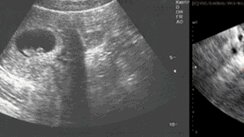

3 неделя беременности – это очень значимый этап, так как в это время внутри вас зарождается новая жизнь. Домашний тест на беременность еще отрицает беременность, но клинический анализ крови уже может сказать о том, что вы беременны. 3 неделя беременности: что происходит у вас в животе? На этой неделе происходит оплодотворение яйцеклетки и зигота (оплодотворенная яйцеклетка) начинает активно делиться и расти. Плодное яйцо постепенно с помощью ворсинок в маточной трубе перемещается в полость матки и прикрепляется к одной из ее стенок...